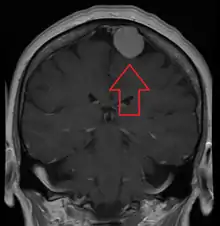

A meningioma that previously had been operated on, with surrounding edema

Meningiomas are visualized readily with contrast CT, MRI with gadolinium,[22] and arteriography, all attributed to the fact that meningiomas are extra-axial and vascularized. CSF protein levels are usually found to be elevated when lumbar puncture is used to obtain spinal fluid. On T1-weighted contrast-enhanced MRI, they may show a typical dural tail sign absent in some rare forms of meningiomas.[17]